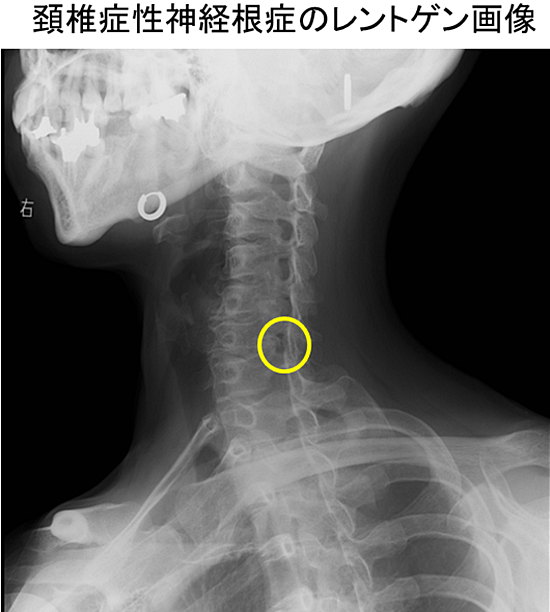

1.レントゲン

レントゲンは骨に異常があるかどうかを調べる検査です。レントゲンでは軟部組織(脳、神経、椎間板など)を検査することは出来ません。レントゲンでは次のようなことがわかります。

- 頚椎全体の形

- 椎体(頚椎の1つの骨)と椎体の間隔の広さ

- 頚椎椎体や椎間関節に骨棘が形成されているか

- 椎間孔(神経が通る孔)の形

- 脊柱管(脊髄が通るところ)の太さ